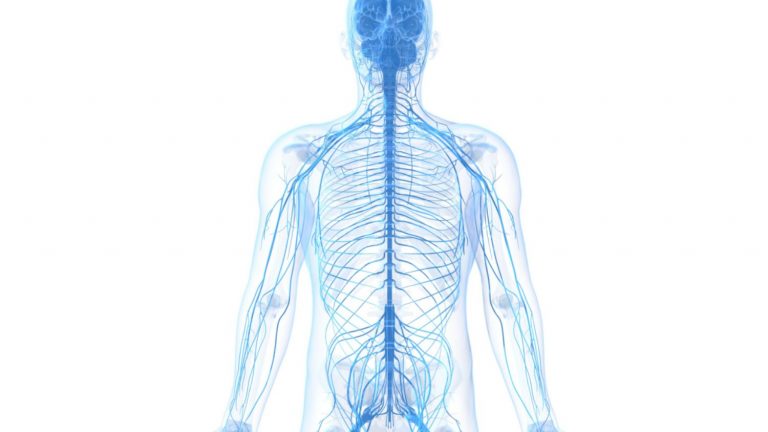

در مجموع دستگاه عصبی شامل مغز، نخاع ، دستگاه های حسی و تمامی اعصاب بدن که این اندام ها را به قسمت های دیگر بدن متصل می کند. اندام ها مسئول کنترل بدن و ارتباط بین قسمت های مختلف آن هستند. مغز و نخاع با نام دستگاه عصب مرکزی...